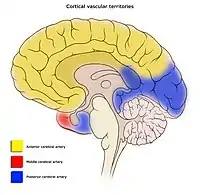

Areas of the brain are supplied by different arteries. The major systems are divided into an anterior circulation (the anterior cerebral artery and middle cerebral artery) and a posterior circulation | |

Blood supply to the brain is normally divided into anterior and posterior segments, relating to the different arteries that supply the brain. The two main pairs of arteries are the Internal carotid arteries (supply the anterior brain) and vertebral arteries (supplying the brainstem and posterior brain).[2]. The anterior and posterior cerebral circulations are interconnected via bilateral posterior communicating arteries. They are part of the circle of Willis, which provides backup circulation to the brain. In case one of the supply arteries is occluded, the circle of Willis provides interconnections between the anterior and the posterior cerebral circulation along the floor of the cerebral vault, providing blood to tissues that would otherwise become ischemic.[3]

Anterior cerebral circulation

The anterior cerebral circulation is the blood supply to the anterior portion of the brain including eyes. It is supplied by the following arteries:

Posterior cerebral circulation

The posterior cerebral circulation is the blood supply to the posterior portion of the brain, including the occipital lobes, cerebellum and brainstem. It is supplied by the following arteries:

Venous drainage

The venous drainage of the cerebrum can be separated into two subdivisions: superficial and deep.

- The superficial system

The superficial system is composed of dural venous sinuses, sinuses (channels) within the dura mater. The dural sinuses are therefore located on the surface of the cerebrum. The most prominent of these sinuses is the superior sagittal sinus which is located in the sagittal plane under the midline of the cerebral vault, posteriorly and inferiorly to the confluence of sinuses, where the superficial drainage joins with the sinus that primarily drains the deep venous system. From here, two transverse sinuses bifurcate and travel laterally and inferiorly in an S-shaped curve that forms the sigmoid sinuses which go on to form the two jugular veins. In the neck, the jugular veins parallel the upward course of the carotid arteries and drain blood into the superior vena cava. The veins puncture the relevant dural sinus, piercing the arachnoid and dura mater as bridging veins that drain their contents into the sinus.[5]

- The deep venous system

The deep venous system is primarily composed of traditional veins inside the deep structures of the brain, which join behind the midbrain to form the great cerebral vein (vein of Galen). This vein merges with the inferior sagittal sinus to form the straight sinus which then joins the superficial venous system mentioned above at the confluence of sinuses.